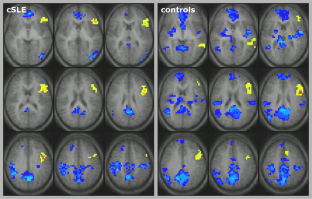

Fig. 1

Fig. 2

50. DiFrancesco MW, Gitelman DR, Klein-Gitelman MS, Sagcal-Gironella ACP, Zelko F, Beebe D, et al. Functional neuronal network activity differs with cognitive dysfunction in childhood-onset systemic lupus erythematosus. Arthritis Res Ther. 2013;15(R40):available online as Provisional PDF.

52. Klein-Gitelman M, Cedeno A, Baker A, Zelko F, Beebe D, Dina B, et al. Brain morphometric changes associated with childhood-onset systemic lupus erythematosus and neurocognitive deficit. Arthritis Rheum-Us. 2011;63(10):S293. This article talks about imaging as a biomarker in lupus.